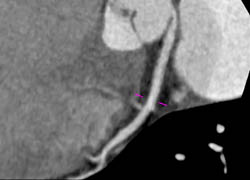

LAD Disease